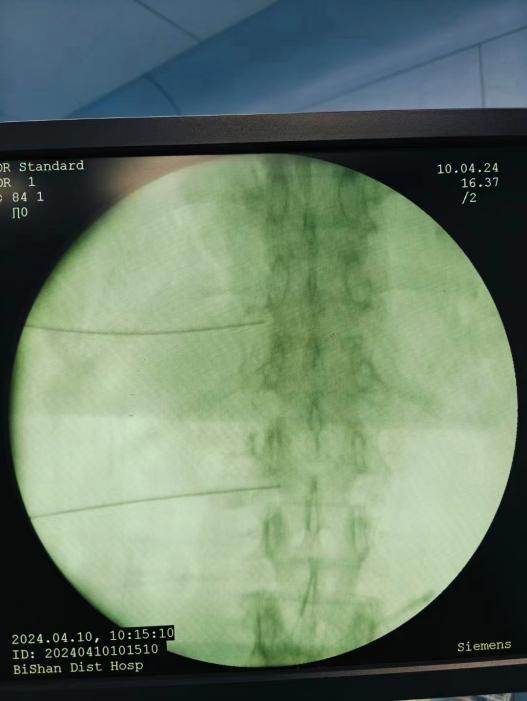

神經阻滯,將藥物在影像引導下注射到受損神經周圍,減輕炎癥和疼痛;

臭氧注射,通過向椎間盤內注射臭氧,氧化髓核內的蛋白多糖,降低椎間盤內壓力,緩解癥狀;

射頻消融治療,連續射頻或脈沖射頻對椎間盤或神經進行干預治療,目的是減小神經根周圍的壓力及對神經的調控治療,從而達到緩解癥狀的效果;